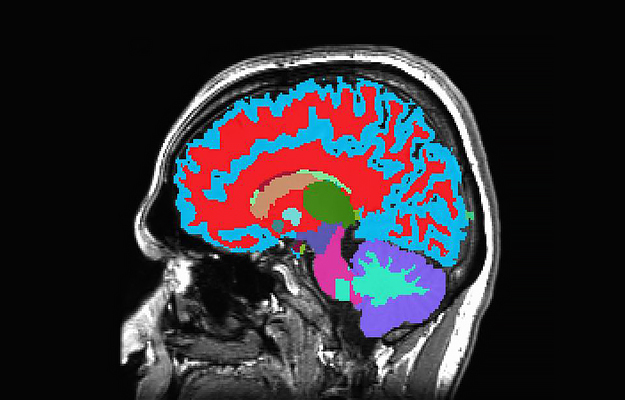

Researchers developed a way to measure how fast a person is aging from a single brain scan. (From NIH Research Matters)